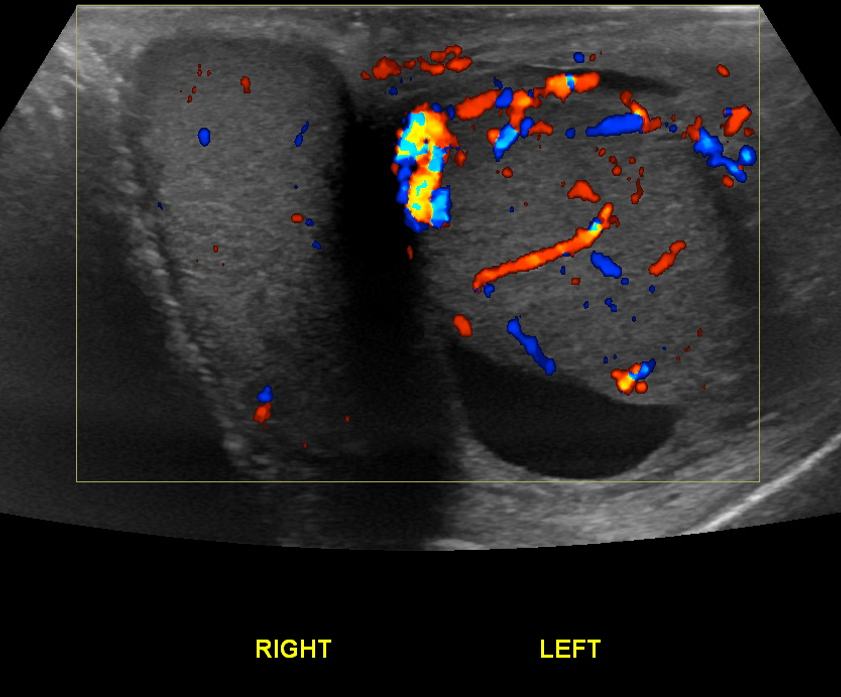

Age: 37

Sex: Male

Indication: Left testicle pain

Epididymo-orchitis

Sample ReportEnlarged left testicle with increased vascularity to the left testicle and epididymis, suggestive of epididymo-orchitis.

Moderate left hydrocele without internal complexity.